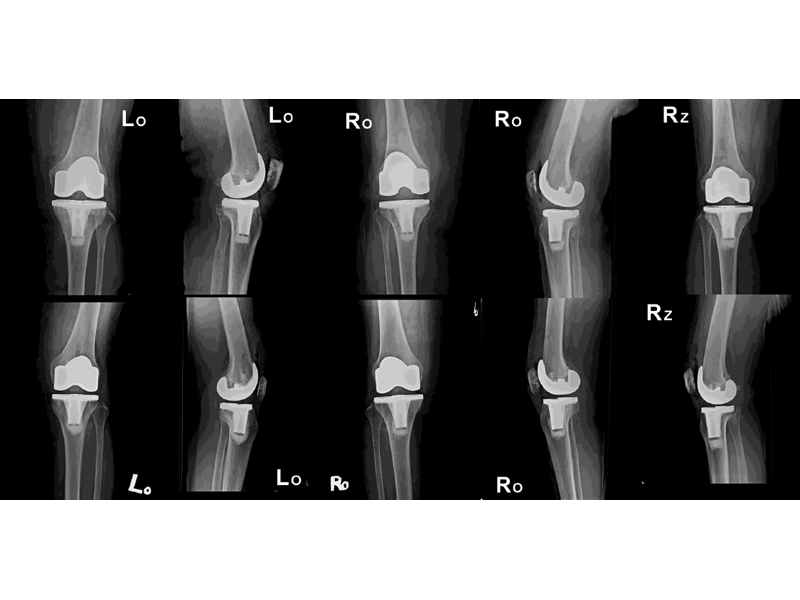

外院失敗本院再置換

更多